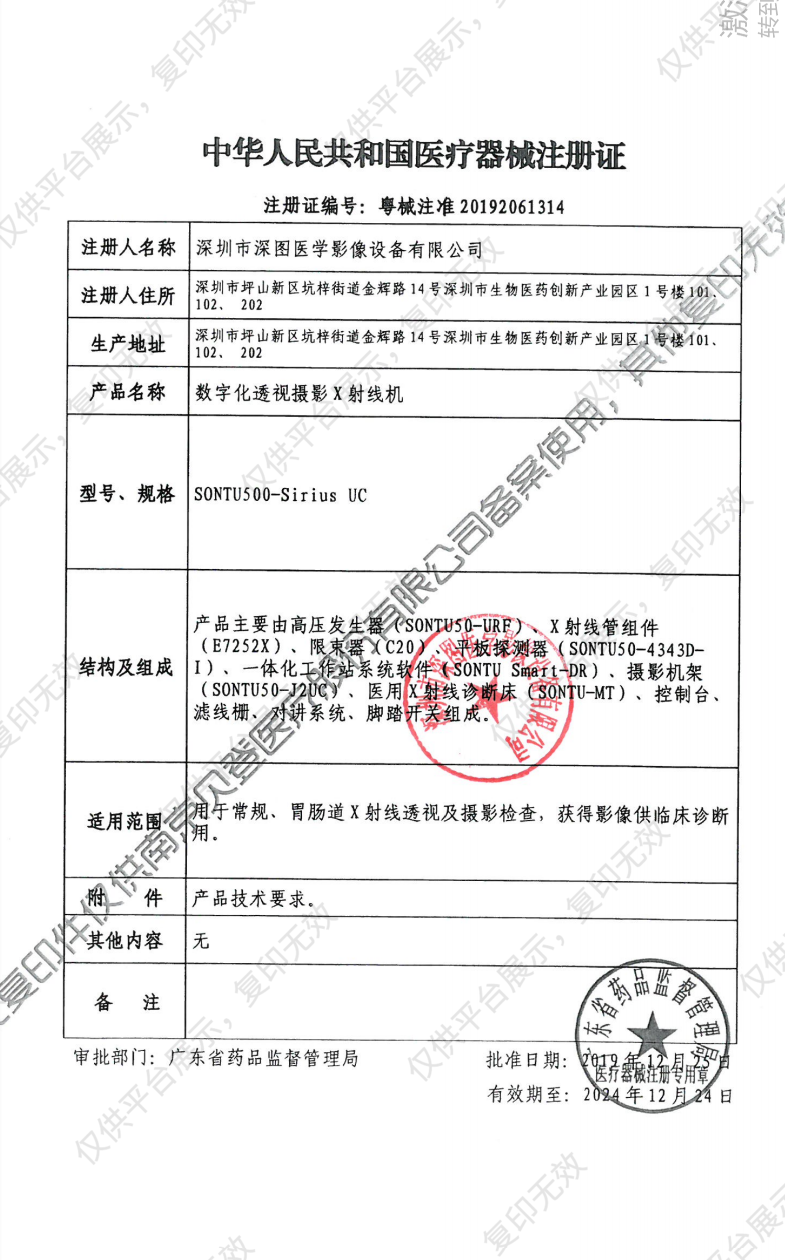

注册信息

- 注册证号: 粤械注准20192061314

- 通用名称: 数字化透视摄影X射线机

深图SONTU 数字化透视摄影X射线机 SONTU500-Sirius UC 注册证

深图SONTU 数字化透视摄影X射线机 SONTU500-Sirius UC 注册证